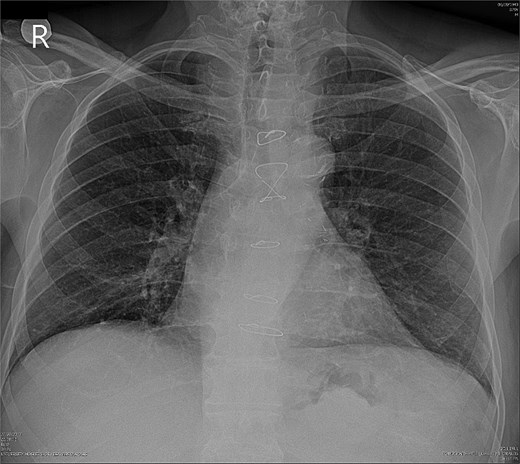

Due to improvement in his symptoms, the patient did not attend his three-month follow-up appointment. Eight months later, the patient was hospitalized with shortness of breath and multiple pulmonary nodules (Fig. 1) on the chest computed tomography (CT) in the pulmonology department of our hospital. Figures 2 and 3 show the preoperative chest X-ray and the chest X-ray taken eight months after the TURP, respectively. Suspected of metastatic disease, a urological evaluation was performed, which revealed an abnormal DRE and a significantly elevated PSA of 134 ng/ml. Diagnostic bronchoscopy and histological findings of the lung biopsy confirmed prostate adenocarcinoma (PCa). TRUS-Bx prostate biopsy (12 cores) confirmed the diagnosis of PCa with involvement of all prostatic cores and Gleason Score (GS) = 8 (4 + 4). Bone scan (Fig. 4) and CT scan were negative for other secondary metastatic lesions in bones and lymph nodes. The patient immediately started combination therapy ADT (degarelix) with apalutamide, and 3 months later, he was off oxygen, and his PSA level had decreased to 14.9 ng/ml.